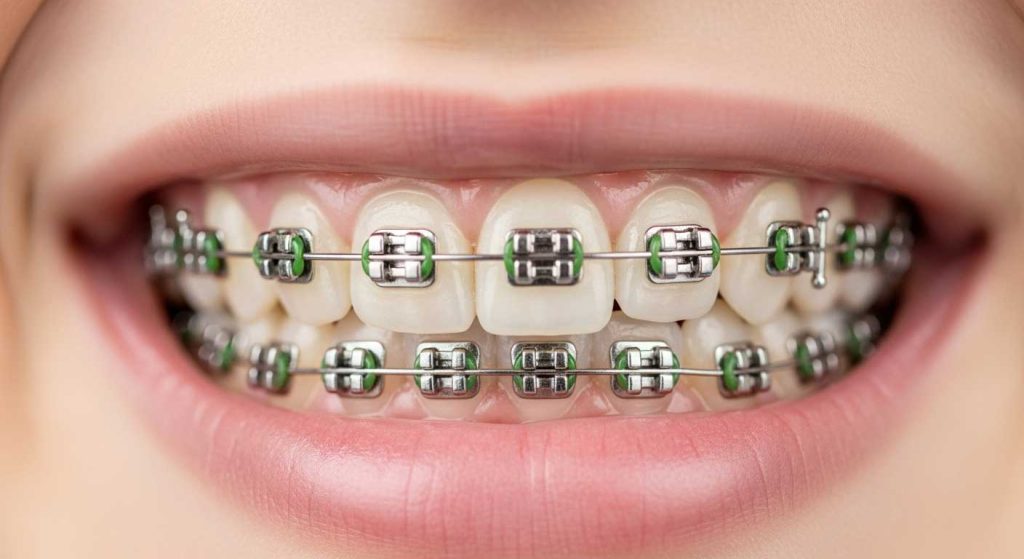

این روش، سنتی ترین و کارآمد ترین نوع درمان است. در ارتودنسی ثابت، براکت ها روی دندان ها چسبانده شده و تا پایان دوره درمان باقی می مانند. این روش برای درمان پیچیده ترین ناهنجاری ها ایده آل است و به دلیل کنترل بالایی که به متخصص می دهد، نتایج بسیار دقیقی به همراه دارد.

اجزای کلیدی بریس ارتودنسی و نقش هر یک

اصلی ترین قطعه، براکت ارتودنسی است که مانند دستگیره ای روی سطح هر دندان چسبانده می شود. این براکت ها شیاری دارند که سیم ارتودنسی از داخل آن عبور می کند. نیروی اصلی حرکت دهنده دندان ها از طریق همین سیم اعمال می شود و براکت ها این نیرو را به تک تک دندان ها منتقل می کنند. از سوی دیگر، کش ارتودنسی که در رنگ های متنوعی وجود دارد، وظیفه نگه داشتن سیم ارتودنسی در داخل شیار براکت ها را بر عهده دارد. علاوه بر این، از کش های خاصی برای اعمال نیرو بین دو فک و اصلاح روابط آن ها استفاده می شود.